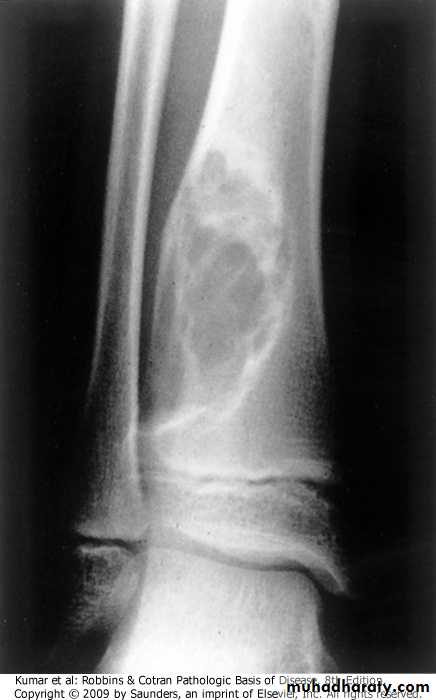

ANURYSMAL BONE CYST:.benign tumor of bone characterized by multiloculated blood-filled cystic spaces.mostly occurs during 1st 2 decades of life, and involves metaphyses of long bones and vertebral bodies.causes pain and swelling, rarely fractures.most lesions are lytic with shell of reactive bone at the periphery

Tibia, aneurysmal bone cyst